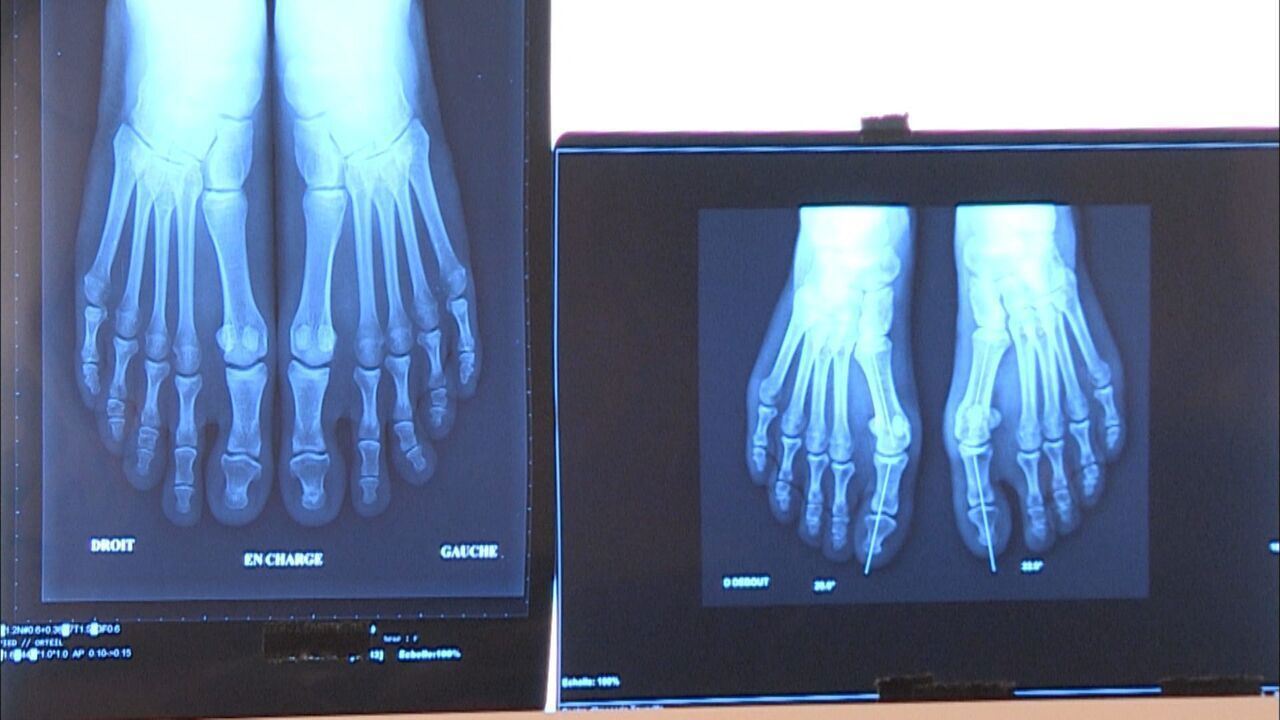

Ortoped dr. Robi Kelc: »Artroza ni konec gibanja, če jo rešujemo pravočasno in celostno«